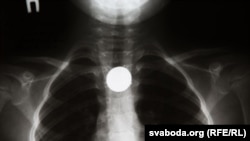

Рентген пищевода белорусского ребенка, проглотившего монету.

Возвращение копеек в массовый оборот в Беларуси привело к неожиданному эффекту: резко участились случаи проглатывания их маленькими детьми. Дело нередко доходит до необходимости обращения в больницы.

Так оно и оказалось. В первые две недели июля в хирургическом отделении Республиканского научного педиатрического центра (РНПЦ) наблюдался наплыв: иногда туда поступало более десяти маленьких пациентов за день. В некоторых случаях процедура по извлечению монет проводится под наркозом. Для этого используется эндоскоп, который вводят в ротовую полость ребенка, чтобы достать монету из желудка или верхней части тонкой кишки.